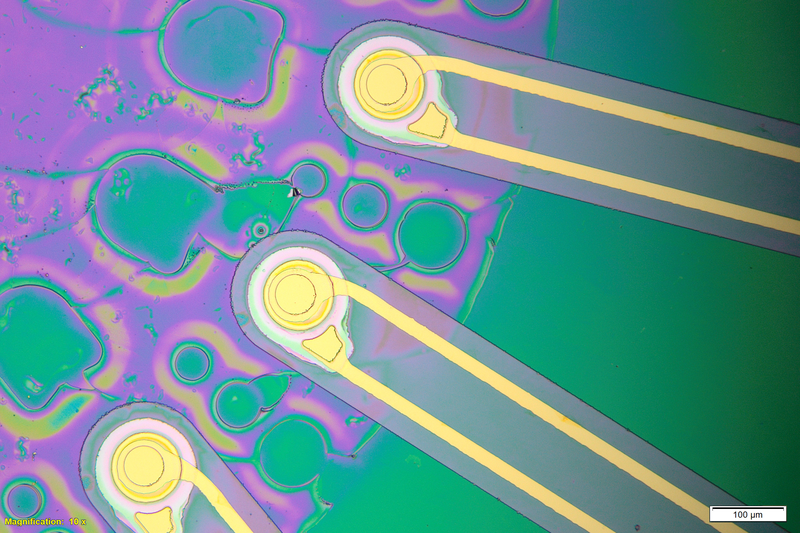

“To precisely modulate neurons, we must go deeper, leading us to design a new kind of ultrasound-based implant that produces localized ultrasound fields,” Nayeem says. To safely reach those deep brain regions, the researchers designed a hair-thin fiber made from a flexible polymer. The tip of the fiber contains a drum-like ultrasound transducer with a vibrating membrane. When this membrane, which encapsulates a thin piezoelectric film, is driven by a small electrical voltage, it generates ultrasonic waves that can be detected by nearby cells.

In tests in mice, the researchers showed that this ultrasound device, which they call ImPULS (Implantable Piezoelectric Ultrasound Stimulator), can provoke activity in neurons of the hippocampus. Then, they implanted the fibers into the dopamine-producing substantia nigra and showed that they could stimulate neurons in the dorsal striatum to produce dopamine.

All of the components of the device are biocompatible, including the piezoelectric layer, which is made of a novel ceramic called potassium sodium niobate, or KNN. The current version of the implant is powered by an external power source, but the researchers envision that future versions could be powered a small implantable battery and electronics unit.

The researchers developed a microfabrication process that enables them to easily alter the length and thickness of the fiber, as well as the frequency of the sound waves produced by the piezoelectric transducer. This could allow the devices to be customized for different brain regions.